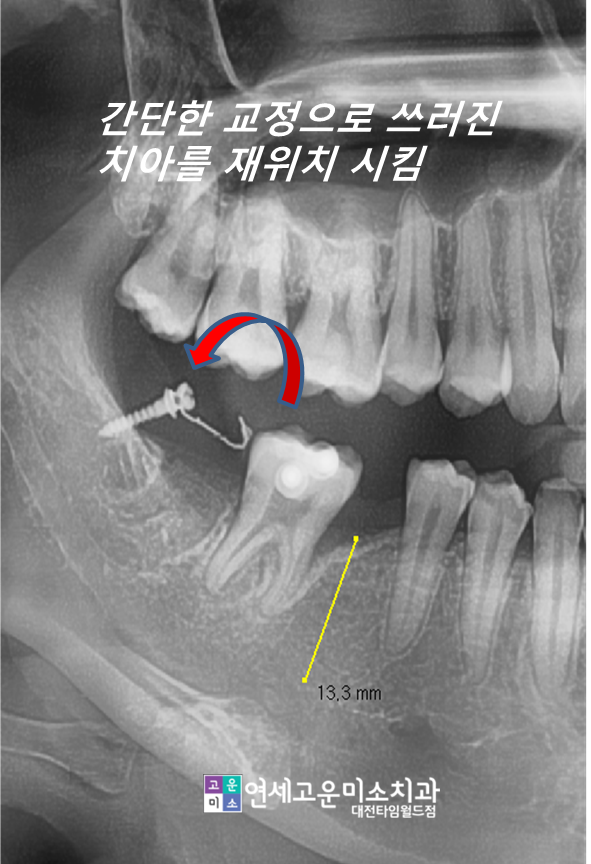

이런 경우 간단한 부분교정으로

해결할 수 있습니다

사랑니를 발치하고 간단한 교정장치를

이용하여 쓰러진 두 번째 큰 어금니를 세웠습니다

기간은 6개월 정도 소요되었습니다